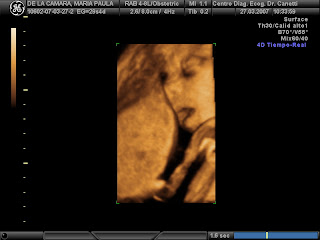

Dale, dejame un primer plano... y se quedó dormidita... ahhhhhhhhh, qué ternura....

Increíble momento...